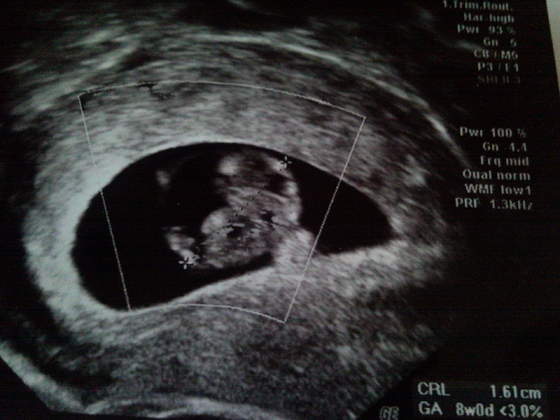

To i ja wrzucam mojego Dzidziola. Jeśli najpierw rozgryzę jak się to robi

Tyle, że mój już nie taki malutki, bo w piątek miał już prawie całe 4cm

Zobacz załącznik 155515

Zdjęcie wkleję później jak M mi zeskanuje